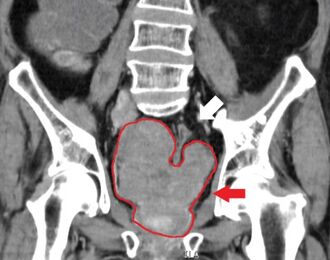

Prostate cancer that has metastasized to the lymph nodes

Prostate cancer that has metastasized to the bone

Prostate cancer is considered a malignant tumor because it can invade other areas of the body. This invasion is called metastasis.[98] Prostate cancer most commonly metastasizes to the bones and lymph nodes, and may invade the rectum, bladder, and lower ureters after local progression.[99] The route of metastasis to bone is thought to be venous, as the prostatic venous plexus draining the prostate connects with the vertebral veins.[100]